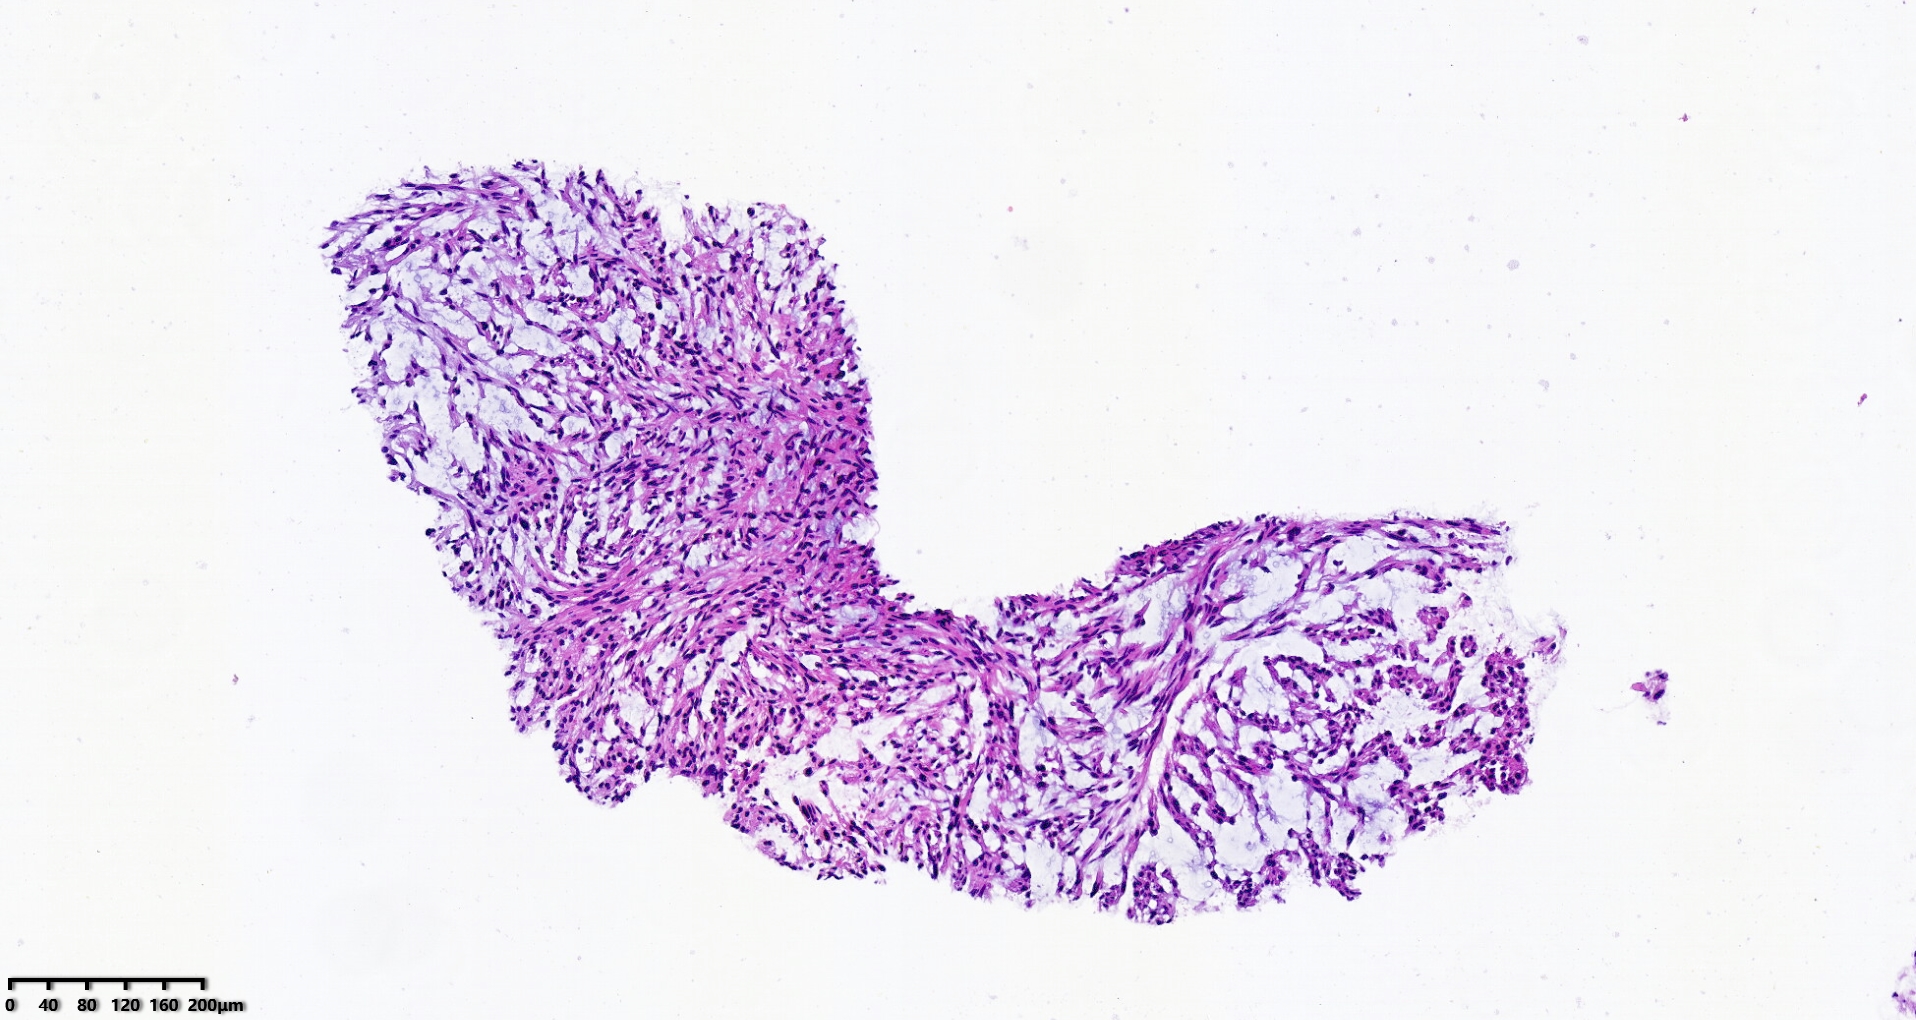

腹盆腔穿刺

性别

男

年龄

70岁

腹盆腔肿物10.5×21.5cm大小

穿刺组织1.0×1.0cm

S100、CD34、MDM2、STAT6、CD117、CK均阴性

考虑:深部软组织平滑肌肉瘤